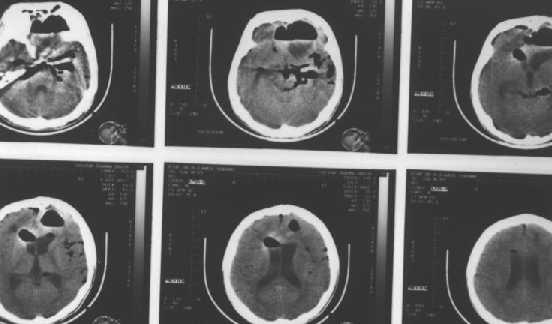

Skull Base fractures : with pneumocephalus